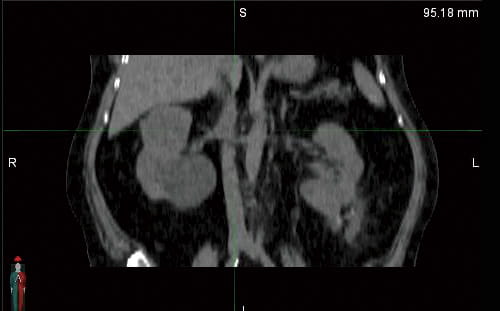

Early Access to New Kidney Cancer PET Scan

We are one of the few cancer centers with early access to this new PET Scan imaging agent for better detection of kidney cancer.

Image of kidneys: PET Scan with new imaging agent (left) compared to CT Scan (right)